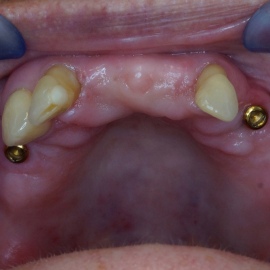

Pacjentka głosiła sie do naszego gabinetu do leczenia z osadzonym mikroimplantem w pozycji lewej dolnej dwójki. Siostrzany implant w pozycji prawej dolnej dwójki wypadł wcześniej, około 1,5 roku od implantacji. Odtworzono przedsionek i dziąsło rogowaciejące, osadzono dwa implanty, jednoczasowo z regeneracją kości. Dopiero na etapie ostatecznej rekonstrukcji protetycznej usunięto zachowany mikroimplant. To się nazywa motywacja do leczenia! Pacjentka przygotowywała sie na ślub prawnuczki :)